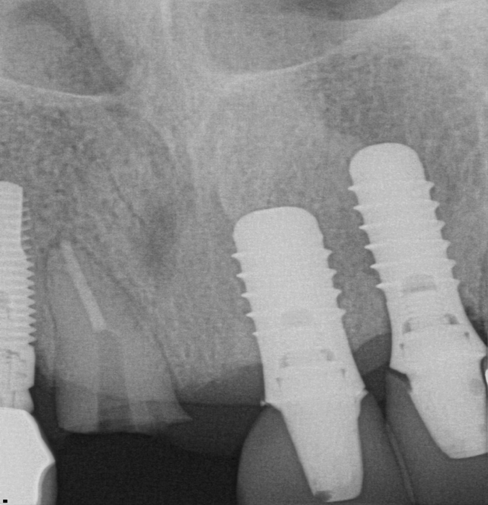

Fig 16. Preoperative periapical radiograph on the day of surgery.

Figure 16